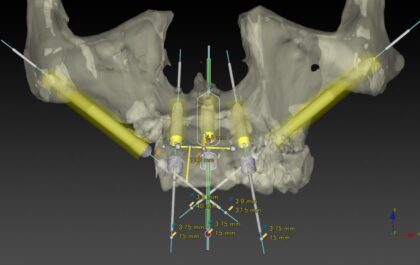

治療計画(シミュレーション)

術前シミュレーション1

術前シミュレーション1

術前シミュレーション2

術前シミュレーション2